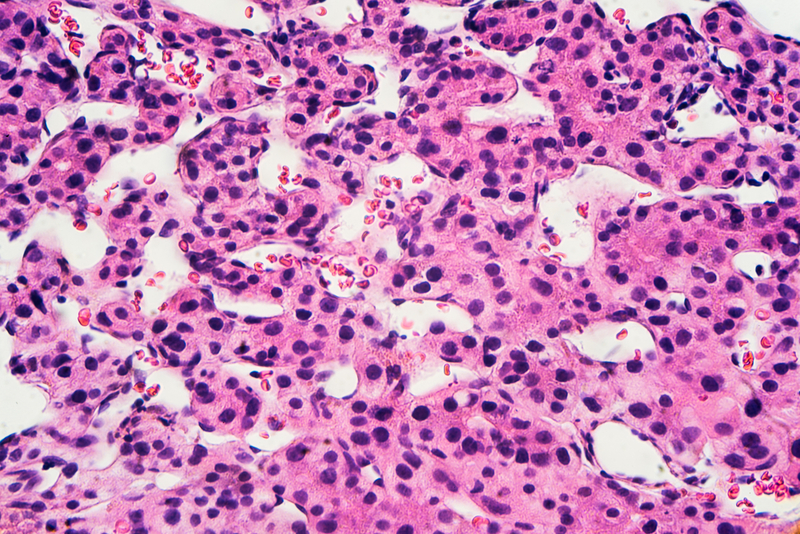

To test whether p38γ is implicated in cell division, study first author Antonia Tomás-Loba examined the outcome of chemically inducing liver cancer in mice that lack the enzyme. The results were truly promising. "In mice lacking p38γ or treated with inhibitors to block its activity, the development of hepatocellular carcinoma was slowed," says Tomás-Loba.

These results, says Sabio, "could be extrapolated to human patients." Indeed, work with colleagues at Salamanca University Hospital shows that the amount of p38γ increases with liver fibrosis, a process that precedes cancer and is much higher in liver cancer patients. These results suggest that in the future it may be possible to treat this type of cancer with drugs that specifically target p38γ. The advantage of targeting p38γ is that this enzyme appears to control the initiation of the cell cycle in response to stress, and therefore inhibiting this process would not affect tissues that are constantly proliferating, like the intestinal lining or hair follicles.